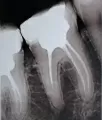

Добрый день! Мне 4 года назад запломбировали зуб. Нервы удалили, металлический штифт поставили и на него потом пломбу. При прикосновении к поверхности зуба языком или другой челюстью, мгновенно возникает адская боль, а десна вокруг него абсолютно безболезненна!

Добрый день, Николай. К сожалению, боли связаны с воспалением на верхушках зуба. Вам необходимо попасть на очный осмотр и сделать рентген-снимки для выявления причин и составления плана лечения!